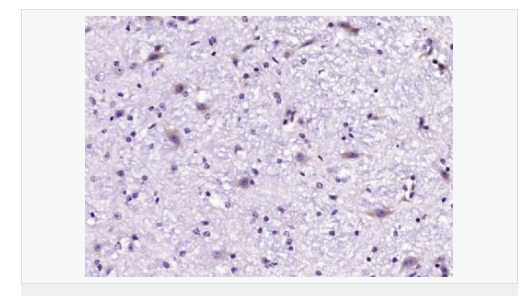

agriculture 的综述文章,对植物中基因组编辑工具的发展和应用进行了系统总结并提出新的发展方向,概述了基于基因组编辑技术的新育种技术的过去、现在以及未来,讨论了基因组编辑技术在促进未来粮食生产时面临的挑战和待解决的问题,为植物育种领域的发展提供了研究亮点。 图 8:来源 Cell 9. Cell:解析甘氨酸受体门控机制 甘氨酸受体广泛分布在突触后的细胞膜上,能介导抑制神经递质的传递,传播抑制信号。 2021 年 2 月 9 日,美国俄勒冈健康科学大学 Eric Gouaux 课题组在 Cell 杂志